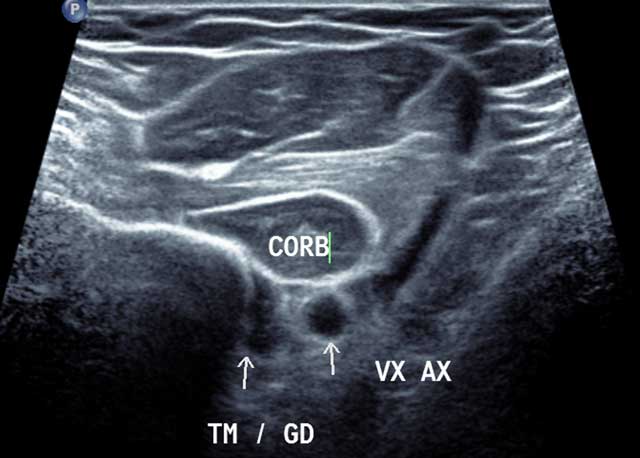

Figure 4

Axial distal section of the anterior and medial humerus area in external rotation. CORB: Coraco Brachal Muscle, TM/GD: Common enthesis of Teres major and Latissimus Dorsi, VX AX: Axillar Artery.